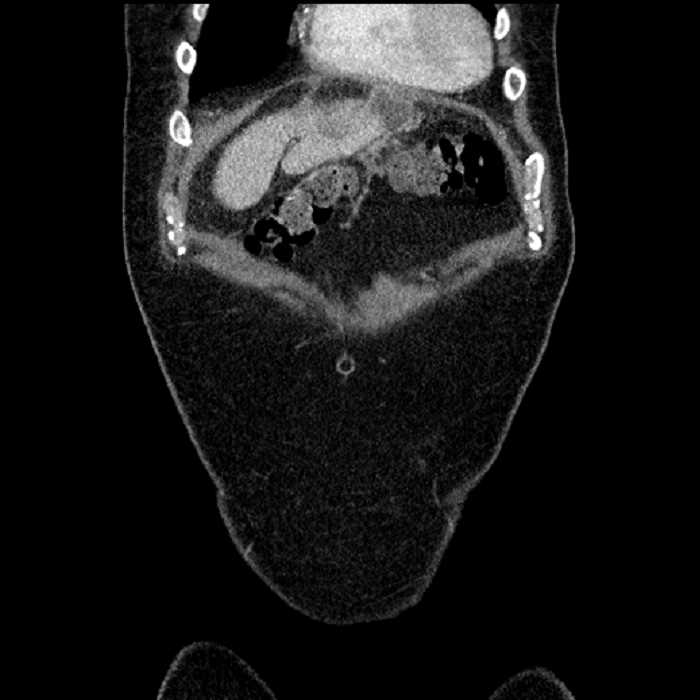

• Mild mural thickening of a segment of the sigmoid colon with adjacent fat stranding and a 1.5 cm fluid and gas collection along the tip of an inflamed diverticulum

• Loss of the normal fat plane between this collection and adjacent loops of small bowel, which demonstrate mural thickening

• No bowel obstruction

Acute sigmoid diverticulitis complicated by a small contained perforation and a large abscess in the right hepatic lobe. Additional small subcapsular abscesses along the anterior margin of the left hepatic lobe.

Additionally, loss of the normal fat plane between the peridiverticular collection and adjacent thickened loops of small bowel raises the potential for an enterocolonic fistula.

Hepatic abscess showing the double target sign with low density internally surrounded by a thin inner enhancing rim (red arrow) and ill-defined outer low density rim (yellow arrow). Blue arrow indicates an internal septation. Red arrows: additional smaller subcapsular abscesses. Red arrow: focal contained perforation associated with diverticulitis.